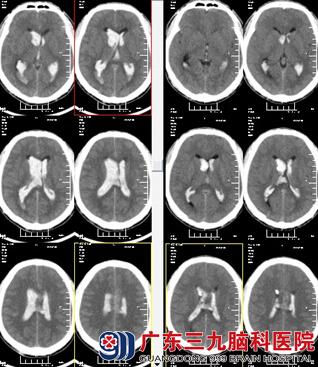

温先生正在上班时候突发头痛、呕吐,随后昏迷,只能发声不能睁眼。同事将温先生送到广东三九脑科医院就诊,头颅CTA示:胼胝体动静脉畸形;双侧脑室内出血;既往史:2009年曾因脑出血治疗,当时诊断为动静脉畸形,具体家属无法提供。

因病情紧急,由林涛主任主刀急诊全麻下为行“脑室外引流术”,术程顺利,术后予以预防感染、止血、脱水、支持、对症等综合治疗,2周后温先生意识逐渐好转。行全脑血管造影术,影像显示:左胼胝体区动静脉畸形;由于畸形较大,一次栓塞术难以处理,需分次进行。告知术中、术后相关风险后,家属表示理解并同意手术后行胼胝体体部动静脉畸形栓塞术,术程顺利,复查造影见动静脉畸形栓塞共约90%。术后复查头颅CT示:呈栓塞术后改变,未见新鲜出血。温先生康复出院。